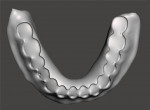

The final design data from the scanned impressions and try-ins were merged and the arches were aligned in the CAD software. Virtual models of the maxillary and mandibular arches were then created (Figure 8 and Figure 9). The virtual models were oriented in the proper VDO and CO positions as established by the scanned try-ins and bite registrations to allow design of the final prosthetics in the optimal orientations (Figure 10). The initial denture tooth positions from the try-in were adapted to the master impression surfaces and final tooth positions that were established during the clinical try-in and bite registration, which were incorporated into the digital design (Figure 11 through Figure 13).

Utilizing the CAD software, digital files were created for each final denture base with sockets correlating to the corresponding denture teeth segments so that each component could be 3D printed separately (Figure 14 through Figure 23). The software was then used to produce virtual denture teeth for the maxillary arch for 3D printing production (Figure 24 through Figure 28). This was then repeated for the mandibular denture teeth arch. The denture bases and teeth were prepared for 3D printing (Figure 29 and Figure 30) and exported for production utilizing a cloud-based 3D printing preparation software (Rayware Cloud, SprintRay).